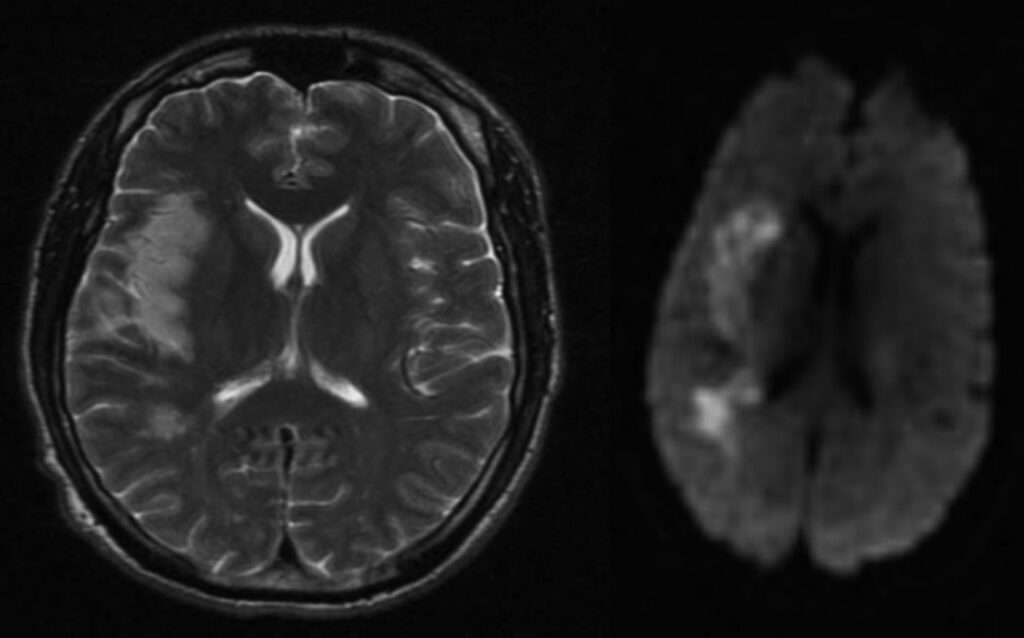

El accidente cerebrovascular es otra complicación temida de la meningitis tuberculosa. Se produce como resultado de una arteritis que afecta a los vasos del polígono de Willis, especialmente a las arterias perforantes que irrigan estructuras profundas del encéfalo, como los ganglios basales y el tálamo. La inflamación de las paredes vasculares conduce a estenosis, trombosis y, en consecuencia, a infartos isquémicos, cuyas secuelas pueden ser graves e irreversibles. Esta vasculopatía se conoce como «vasculitis de las arterias perforantes» y es una de las principales causas de déficit neurológico focal en estos pacientes.

Además, la obstrucción del flujo normal del líquido cefalorraquídeo constituye una complicación estructural crítica. El exudado denso y caseoso que se acumula en las cisternas basales puede bloquear la circulación del líquido cefalorraquídeo, particularmente a nivel de los ventrículos y de los acueductos, dando lugar a una hidrocefalia de tipo obstructivo. Esta condición se manifiesta clínicamente con signos de hipertensión intracraneal, como cefalea, vómitos y alteraciones del estado de conciencia, y puede evolucionar hacia un deterioro cognitivo progresivo si no se trata de manera oportuna, por ejemplo, mediante derivación ventricular.